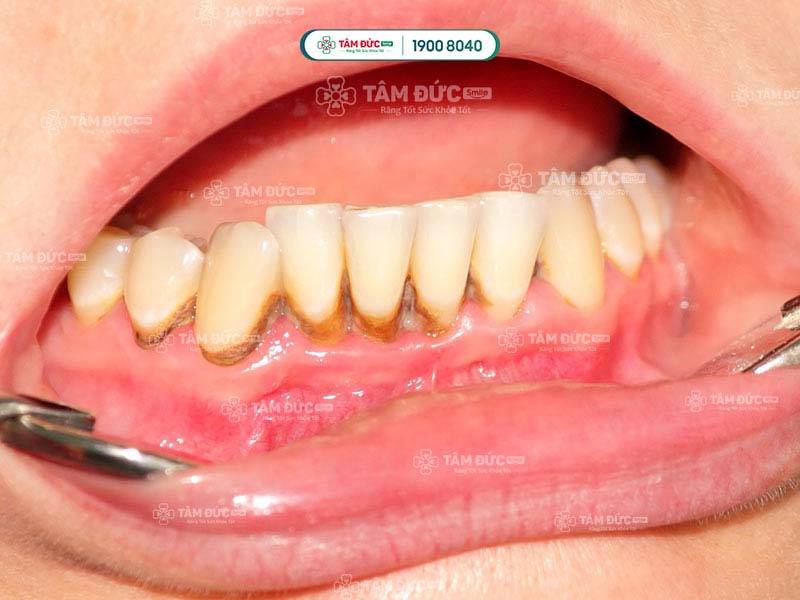

Cao răng được phân chia thành nhiều cấp độ khác nhau, tùy thuộc vào mức độ nghiêm trọng của chúng. Trong đó, cao răng độ 3 là mức độ nghiêm trọng và chỉ đứng sau cấp độ 4. Lúc này, mảng bám đã phát triển dày hơn 2 mm, cứng và bám chặt ở trên răng. Chúng thường có màu vàng sẫm hoặc nâu đậm, Quý khách không thể làm sạch cao răng bằng những phương pháp vệ sinh răng miệng thông thường. Chính điều này đã làm giảm đi tính thẩm mỹ của hàm răng, khiến nhiều người cảm thấy mất tự tin trong quá trình giao tiếp.

Cao răng độ 3 là mảng bám đã phát triển dày hơn 2mm, cứng và bám chặt ở trên răng

Cao răng ở độ 3 thường có màu vàng đậm hoặc nâu, nâu nhạt. Những màu sắc này tương phản với màu răng thật làm tổng thể hàm răng của Quý khách không được đều màu, mất đi tính thẩm mỹ. Một số trường hợp cao răng còn lan ra ở phía ngoài, lộ rõ ở chân răng, bề mặt răng. Đây là lý do khiến nhiều người cảm thấy tự ti trong giao tiếp, công việc.

Cao răng độ 3 có màu vàng đậm, nâu, nâu nhạt gây mất thẩm mỹ